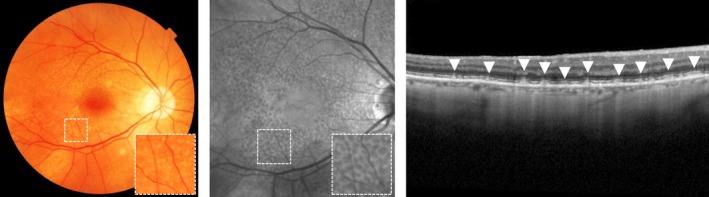

Age-related macular degeneration (AMD) is a degenerative disease of the macula, often leading to progressive vision loss. The rate of disease progression can vary among individuals and has been associated with multiple risk factors. In this review, we provide an overview of the current literature investigating phenotypic, demographic, environmental, genetic, and molecular risk factors, and propose the most consistently identified risk factors for disease progression in AMD based on these studies. Finally, we describe the potential use of these risk factors for personalised healthcare.

While phenotypic risk factors such as drusen and pigment abnormalities become more important to predict disease progression during the course of the disease, demographic, environmental, genetic and molecular risk factors are more valuable at earlier disease stages. Demographic and environmental risk factors such as age and smoking are consistently reported to be related to disease progression, while other factors such as sex, body mass index (BMI) and education are less often associated. Of all known AMD variants, variants that are most consistently reported with disease progression are rs10922109 and rs570618 in CFH, rs116503776 in C2/CFB/SKIV2L, rs3750846 in ARMS2/HTRA1 and rs2230199 in C3. However, it seems likely that other AMD variants also contribute to disease progression but to a lesser extent. Rare variants have probably a large effect on disease progression in highly affected families. Furthermore, current prediction models do not include molecular risk factors, while these factors can be measured accurately in the blood. Possible promising molecular risk factors are High-Density Lipoprotein Cholesterol (HDL-C), Docosahexaenoic acid (DHA), eicosapentaenoic acid (EPA), zeaxanthin and lutein.